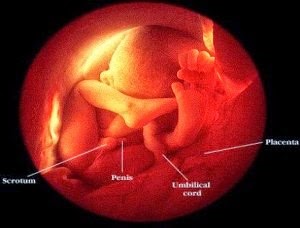

Janin berusia dua belas minggu

Panjang janin lebih kurang 7.6 cm dengan berat 28 gram. Kepala bayi

menjadi lebih bulat dan wajah telah terbentuk sepenuhnya. Jari-jari tangan dan

kaki mulai terbentuk, dan kuku juga tumbuh. Bayi mulai menggerak-gerakkan bahu

dan lengannya, tetapi ibu belum dapat merasakan gerakan-gerakan ini. Pada ketika ini jantina bayi telah dapat

dikenal pasti.